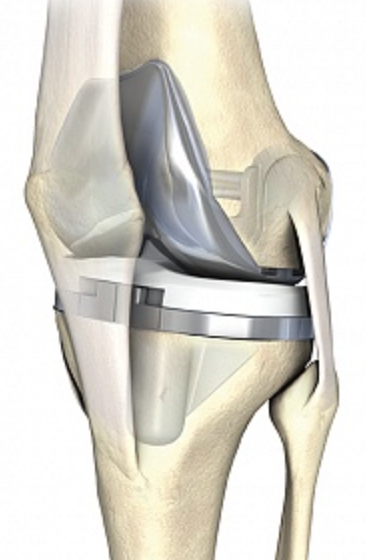

C’est vers le milieu du 20ème siècle que la forme que nous connaissons aux prothèses articulaires actuellement a été fixée. La principale révolution a eu lieu au niveau de la hanche et provient de deux chirurgiens orthopédistes : le Suisse Maurice-Étienne Müller de Berne et le Britannique Sir John Charnley. Ils ont conçu une prothèse articulaire transformant une hanche naturelle qui relie une grosse tête de fémur (pouvant aller de 44 mm à 62 mm) et un cotyle, en une tête métallique de 22 ou 28 mm portée par une tige scellée dans le fémur et articulée avec une cupule en polyéthylène PE (cf. infra) scellée dans le bassin : c’est le concept du Low Friction torque Arthroplasty (LFA), autrement dit le couple de faible friction tribologique. En effet, jusque dans ces années 1960, les prothèses tâchaient de reproduire tout bonnement la hanche naturelle telle quelle. La conséquence est une faible épaisseur de PE dans le cotyle prothésé, or nous n’étions pas encore à l’époque du PE de haute densité comme aujourd’hui. Le résultat est une usure rapide de la cupule en PE (qui est littéralement laminée par la tête prothétique) avec relargage des particules de polyéthylène responsables d’une réaction de la part des cellules de défense de l’organisme aboutissant à un descellement de la prothèse. C’est également au début de ces années 60 que le ciment acrylique a été introduit. C’est du poly méthyl méta acrylate qui, en se polymérisant devient dur et permet de sceller les implants dans l’os. Le prix à payer pour ce modèle de « petite tête fémorale » dans une « petite cupule cotyloïdienne » est l’instabilité avec des luxations. Pour y pallier, des cupules dites rétentives ont été introduites avec comme conséquence, l’augmentation des contraintes sur le PE dont le corollaire est l’usure – descellement. Jusque dans les années 90, la durée de vie des prothèses était autour de 10 ans.

Actuellement, l’amélioration de la qualité des matériaux ainsi que de leur usinage, surtout le polissage de la surface de friction, ont permis de porter la durée de vie des prothèses au-delà de 30 ans. Trois catégories de matériaux sont actuellement utilisées. Il s’agit des alliages métalliques, des céramiques et du polyéthylène de haute densité. Des essais d’implants en carbone sont en cours.

Les alliages métalliques sont essentiellement en chrome – cobalt et en titane. Les céramiques sont des matériaux non métalliques et non organiques obtenus par l’effet de fortes températures sur de l’alumine ou du zircon. Le polyéthylène est un matériau plastique issu de l’industrie pétrochimique. Il sert à constituer la surface de friction des implants. L’introduction du ciment acrylique dans la fixation des implants à l’os date du début des années 60. Depuis le milieu des années 80, le concept de prothèse sans ciment est apparu. Le principe consiste à recouvrir la surface de contact des implants avec l’os d’un revêtement dit ostéo-conducteur. Il s’agit de l’hydroxyapatite, un composant minéral naturel de l’os que l’on produit artificiellement. Au contact de la prothèse, l’os du voisinage identifie cet hydroxyapatite comme un de ses propres constituants et le colonise. La prothèse devient ainsi intégrée à l’os. On parle alors de stabilité secondaire. Naturellement, en attendant cette repousse d’os sur le revêtement d’hydroxyapatite, la stabilité primaire est assurée par l’impaction en force de la prothèse dans l’os et éventuellement fixée par des vis complémentaires. Les couples de friction (surface de frottement des implants) sont de plusieurs sortes : métal – PE, céramique – PE, céramique – céramique. Le couple métal – métal dit de gros diamètre a été utilisé au moins durant trois périodes depuis le 20ème siècle dont la dernière au-début des années 2000 avant d’être à nouveau abandonné pour cause de relargage excessif de particules de métal dans l’organisme.